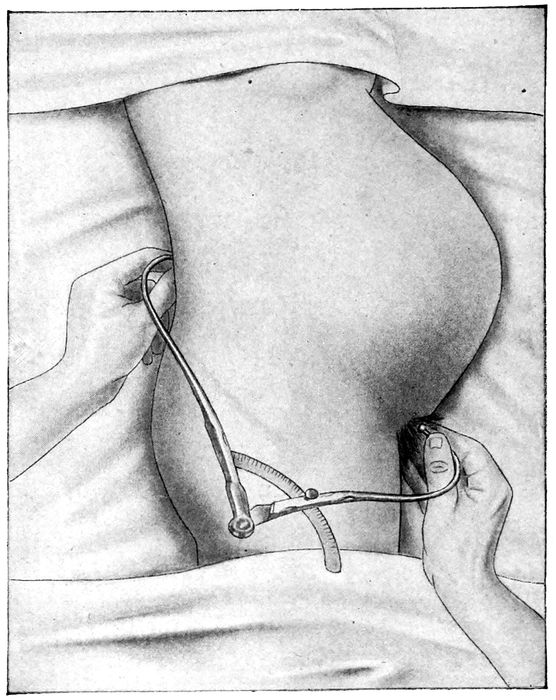

| 97. |

Measuring the external conjugate |

218 |

| |

| 98. |

Measuring the diagonal conjugate with the finger |

219 |

| |